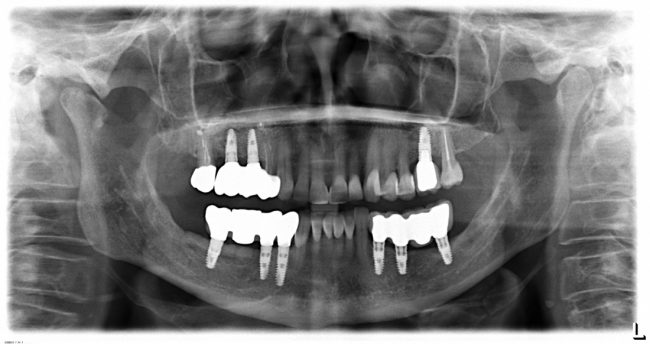

Состояние имплантатов, протетики, десны вокруг имплантатов более, чем удовлетворительное. Да, хотелось бы картинку пофотогеничнее, но Елена не испытывает с протетикой никаких проблем, гигиена удовлетворительная, качество жизни на уровне — чего еще желать? Вот контрольная ортопантомография через три с половиной года после протезирования:

Собственно, больше пяти лет после остеопластики и имплантации, через три с половиной года после протезирования — и никаких негативных изменений. Объемы и состояние костной ткани в области имплантатов оказалось более устойчивыми, чем я изначально предполагал, что говорит о восстановлении её кровоснабжения и регенерации. Сравним снимки: